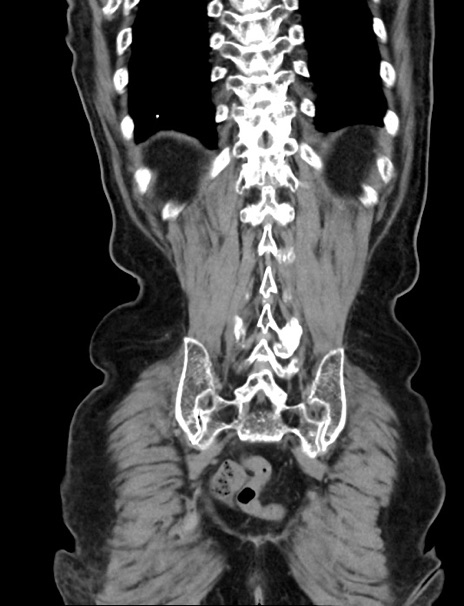

症例33(冠状断像)

【症例】70歳代 女性

【主訴】心窩部痛

【現病歴】延髄病変の精査・加療にて神経内科入院中。本日より心窩部痛あり。

【既往歴】虫垂炎

【身体所見】右下腹部を中心に圧痛と反跳痛あり。

【データ】WBC 10900、CRP 0.02